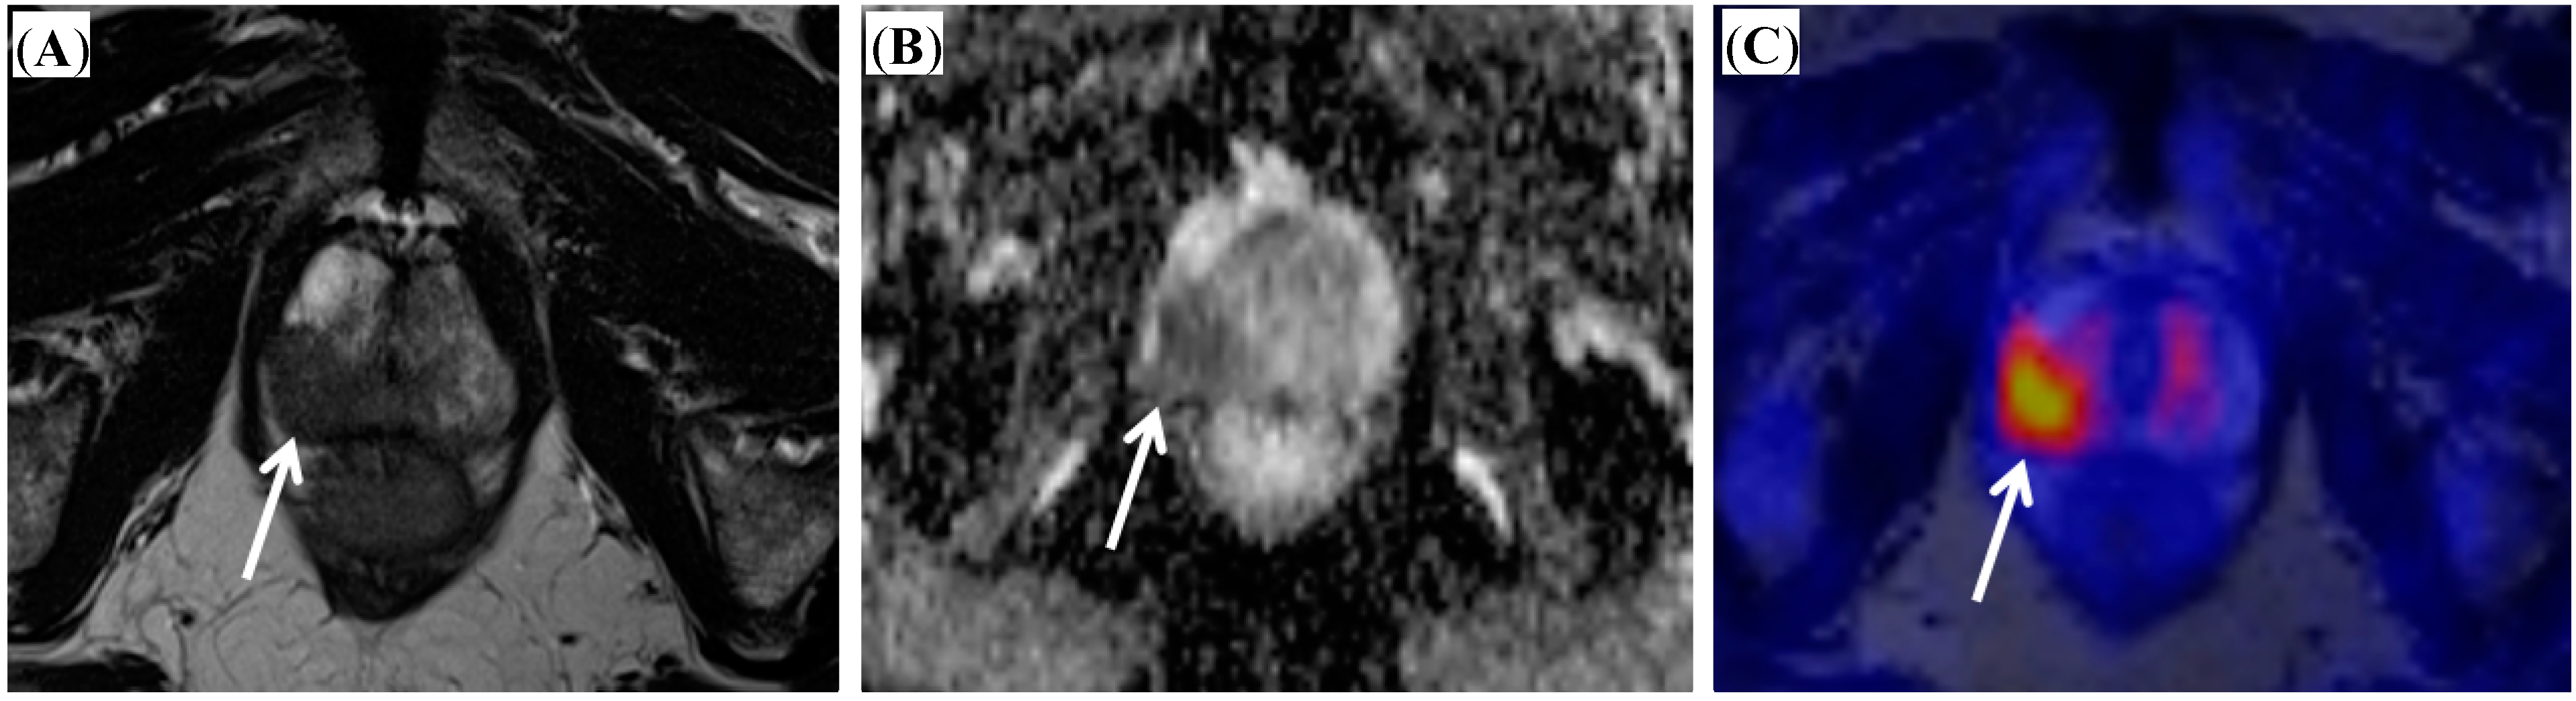

- Wetter, A.; Lipponer, C.; Nensa, F.; Beiderwellen, K.; Tobias, O.; Rubben, H.; Bockisch, A.; Schlosser, T.; Heusner, T.A.; Lauenstein, T.C. Simultaneous 18F choline positron emission tomography/magnetic resonance imaging of the prostate: Initial results. Investig. Radiol. 2013, 48, 256–262. [Google Scholar] [CrossRef]

- Wetter, A.; Lipponer, C.; Nensa, F.; Heusch, P.; Rubben, H.; Altenbernd, J.-C.; Schlosser, T.; Bockisch, A.; Poppel, T.; Lauenstein, T.; et al. Evaluation of the PET component of simultaneous [18F] choline PET/MRI in prostate cancer: Comparison with [18F] choline PET/CT. Eur. J. Nucl. Med. Mol. Imaging 2014, 41, 79–88. [Google Scholar] [CrossRef]

- Hartenbach, M.; Hartenbach, S.; Bechtloff, W.; Danz, B.; Kraft, K.; Klemenz, B.; Sparwasser, C.; Hacker, M. Combined PET/MRI improves diagnostic accuracy in patients with prostate cancer: A prospective diagnostic trial. Clin. Cancer Res. 2014, 20, 3244–3255. [Google Scholar] [CrossRef]

- De Perrot, T.; Rager, O.; Scheffler, M.; Lord, M.; Pusztaszeri, M.; Iselin, C.; Ratib, O.; Vallee, J.-P. Potential of hybrid 18F-fluorcholine PET/MRI for prostate cancer imaging. Eur. J. Nucl. Med. Mol. Imaging 2014. [Google Scholar] [CrossRef]